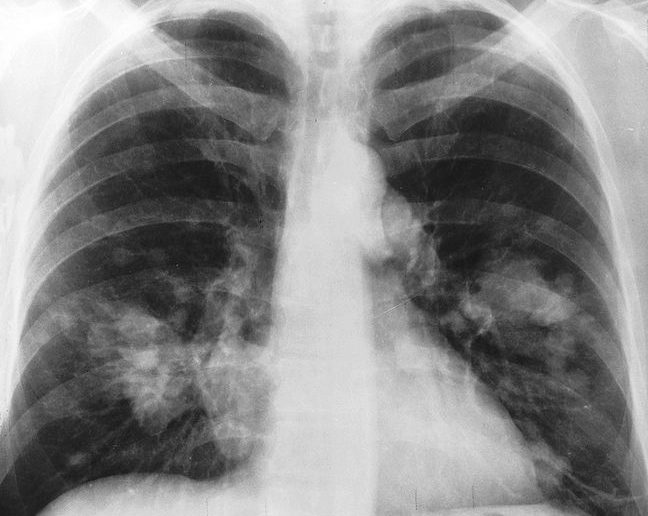

X-ray image courtesy of Wikimedia